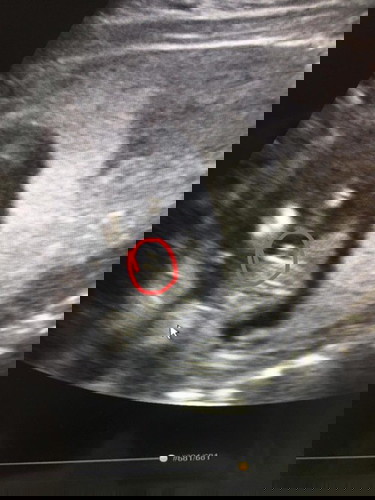

ดีใจได้ลูกชายค่ะ แม่ๆคนไหนทราบเพศลูกกันหรือยังคะ

วันนี้รู้เพศลูกอายุครรภ์ 16 สัปดาห์ 2 วัน ดีใจจร้า